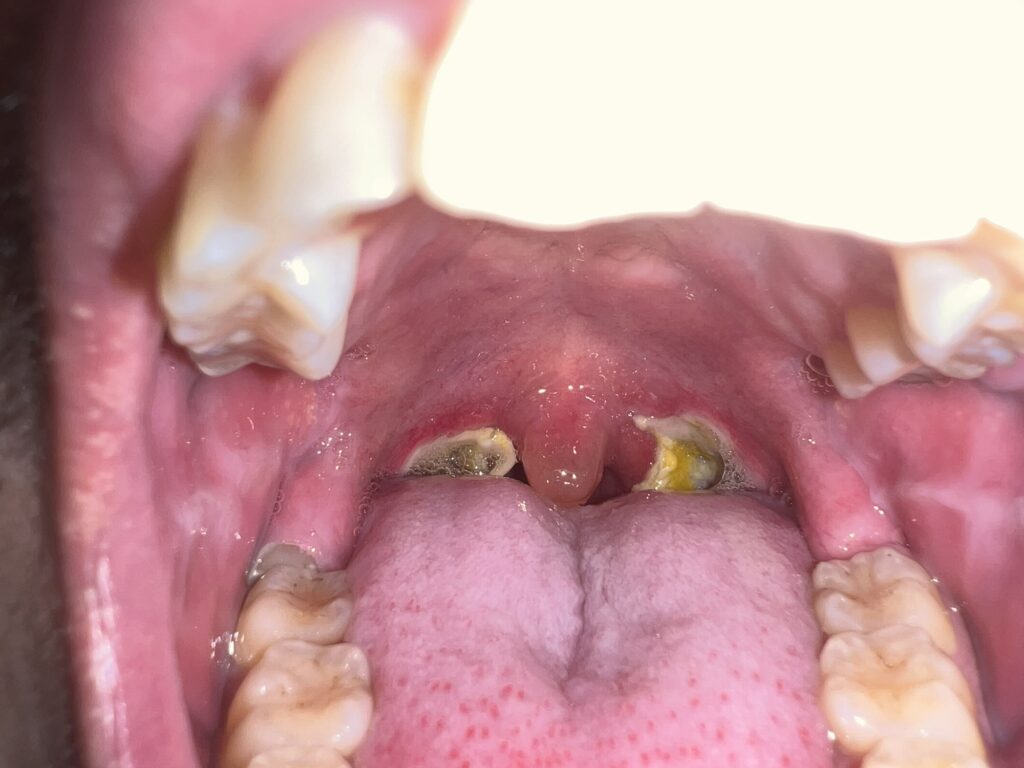

11月17日(手術前)

手術前夜に記念にとパシャリ。中学校2年生の時から共に過ごしてきたポリープちゃんの見納めです。さようなら。